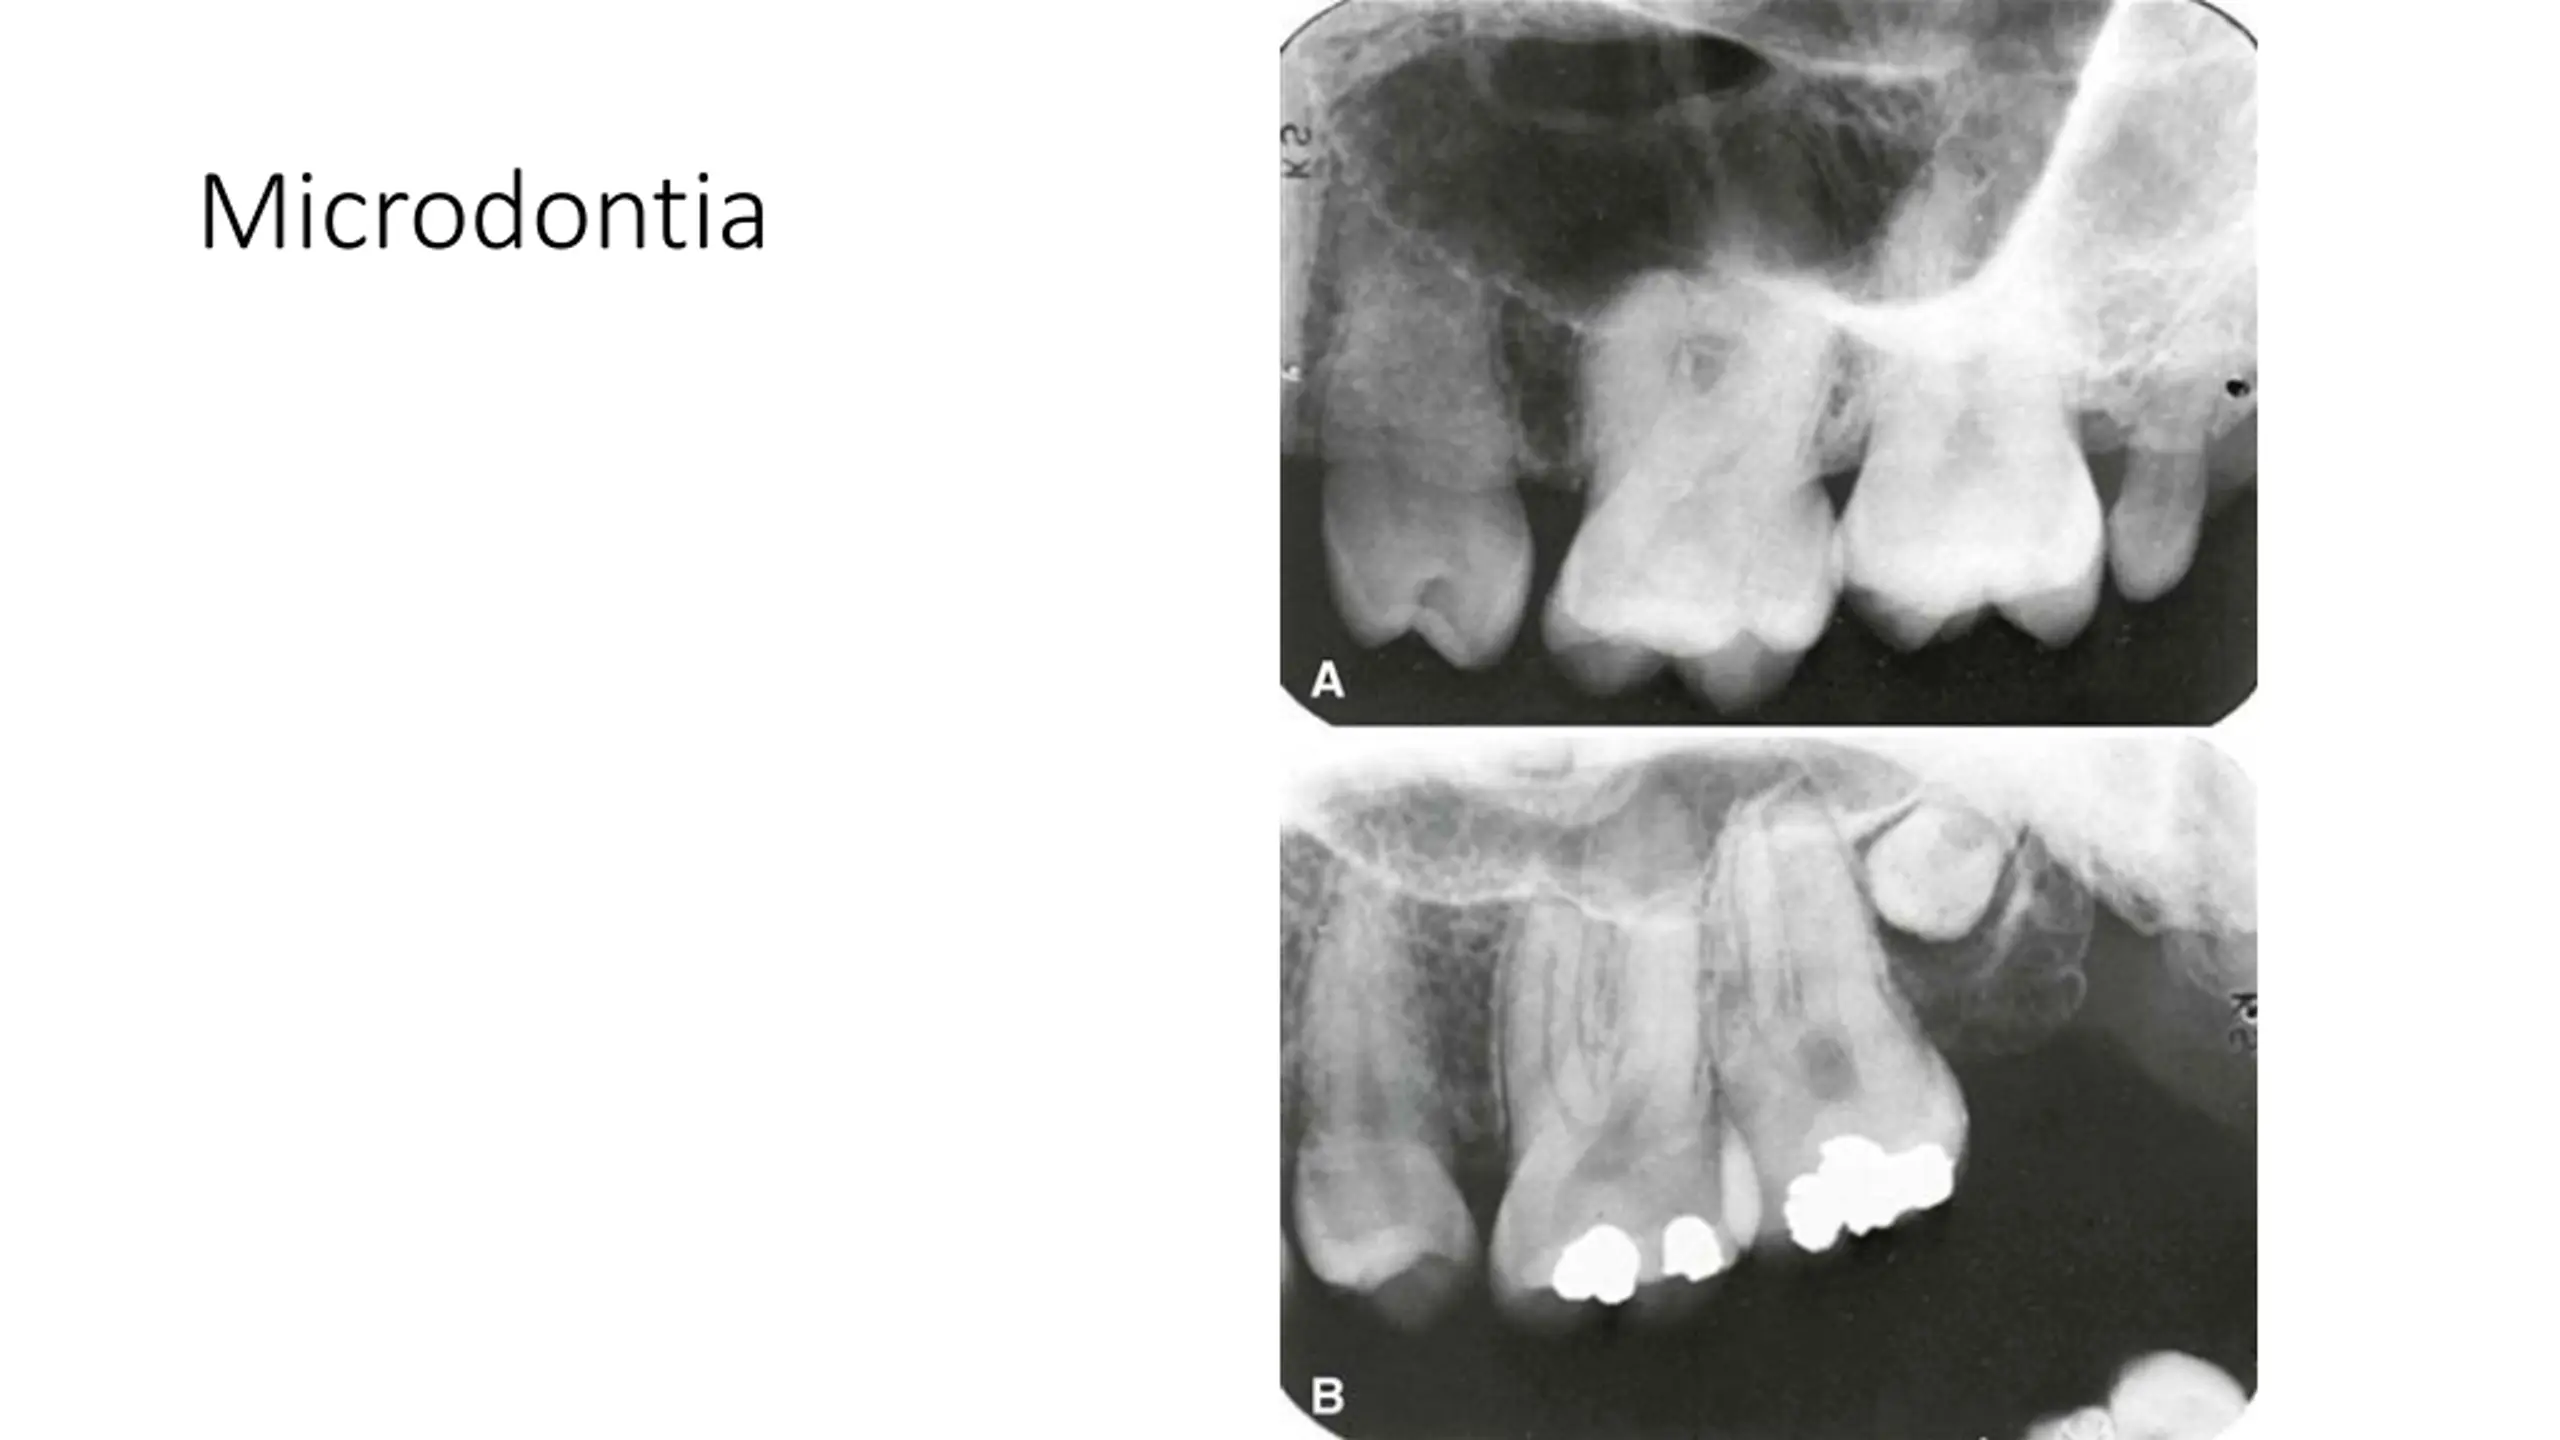

True Anodontia, Partial True Anodontia, Partial False Anodontia, Mesiodens/Supernumerary, Microdontia, Marcrodontia, Gemination/Right Fusion/Left, Peg-Lateral, Fusion Two Roots/Two Crowns, Dens in dente, Dilaceration, Concresences, Taurodontia, Hypercementosis, Amelogenesis Imperfecta, Dentinogenesis Imperfecta, Hutchinson Incisors, Mulberry Molars, Mental Foramens - Radiolucent.